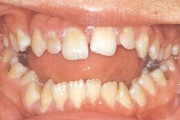

Lutipudelikaariese kahjustused

Lutipudelikaaries